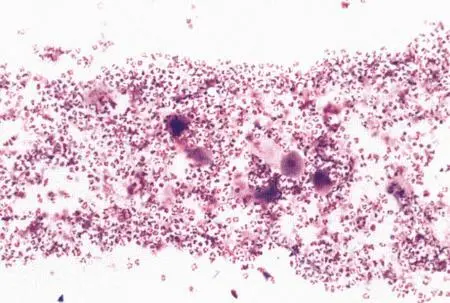

Рассматриваются следующие вопросы: нормальная физиология собак и кошек; болезни репродуктивной системы; бесплодие самок и бесплодие самцов; нормальное функционирование и дисфункция молочных желез; спаривание; искусственное осеменение; протекание беременности и роды; уход за новорожденными щенками и котятами, их наследственные и инфекционные болезни; техника оперативных вмешательств на репродуктивных органах; фармакологический контроль репродукции.